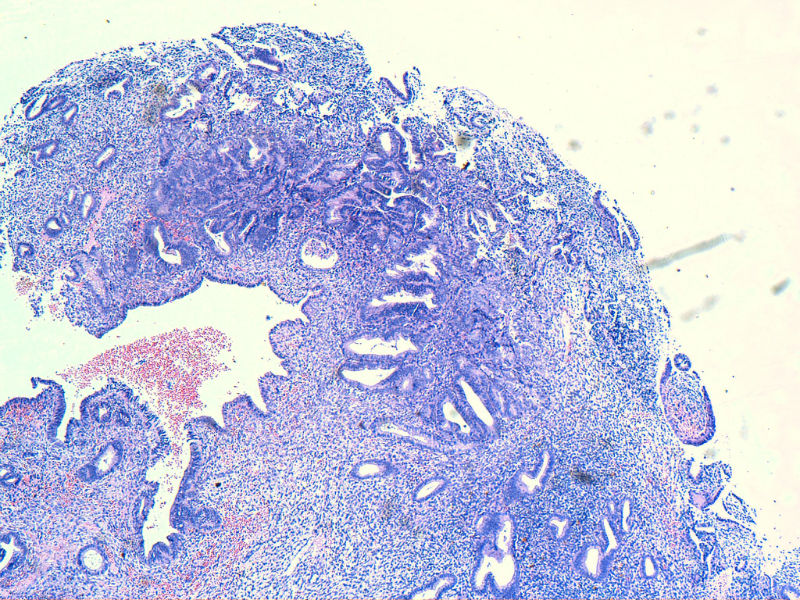

图13是做为正常对照的,图7、8、9、12显示的核大小不一,空泡状,形状不规则。女,48岁,宫血半年